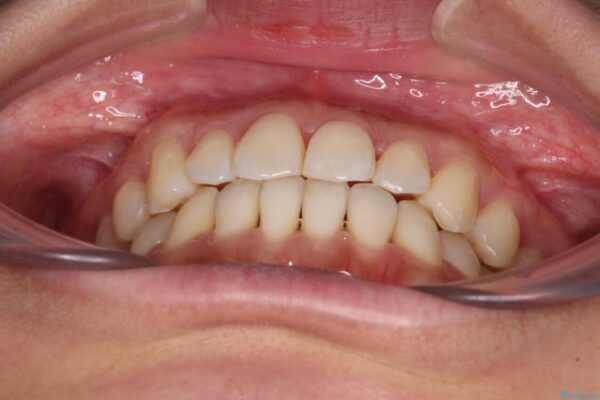

前歯のデコボコで前方に出ていることを気にして来院された患者様です。

上顎前歯が捻れて前方に飛び出しており、下顎前歯もそれに沿うようにデコボコとなっていました。

IPR(歯と歯の間を削る処置)によりスペースを獲得して上下顎前歯のデコボコを改善し、飛び出している前歯が引っ込むように設定し、インビザラインにて矯正治療を行うこととしました。

治療前